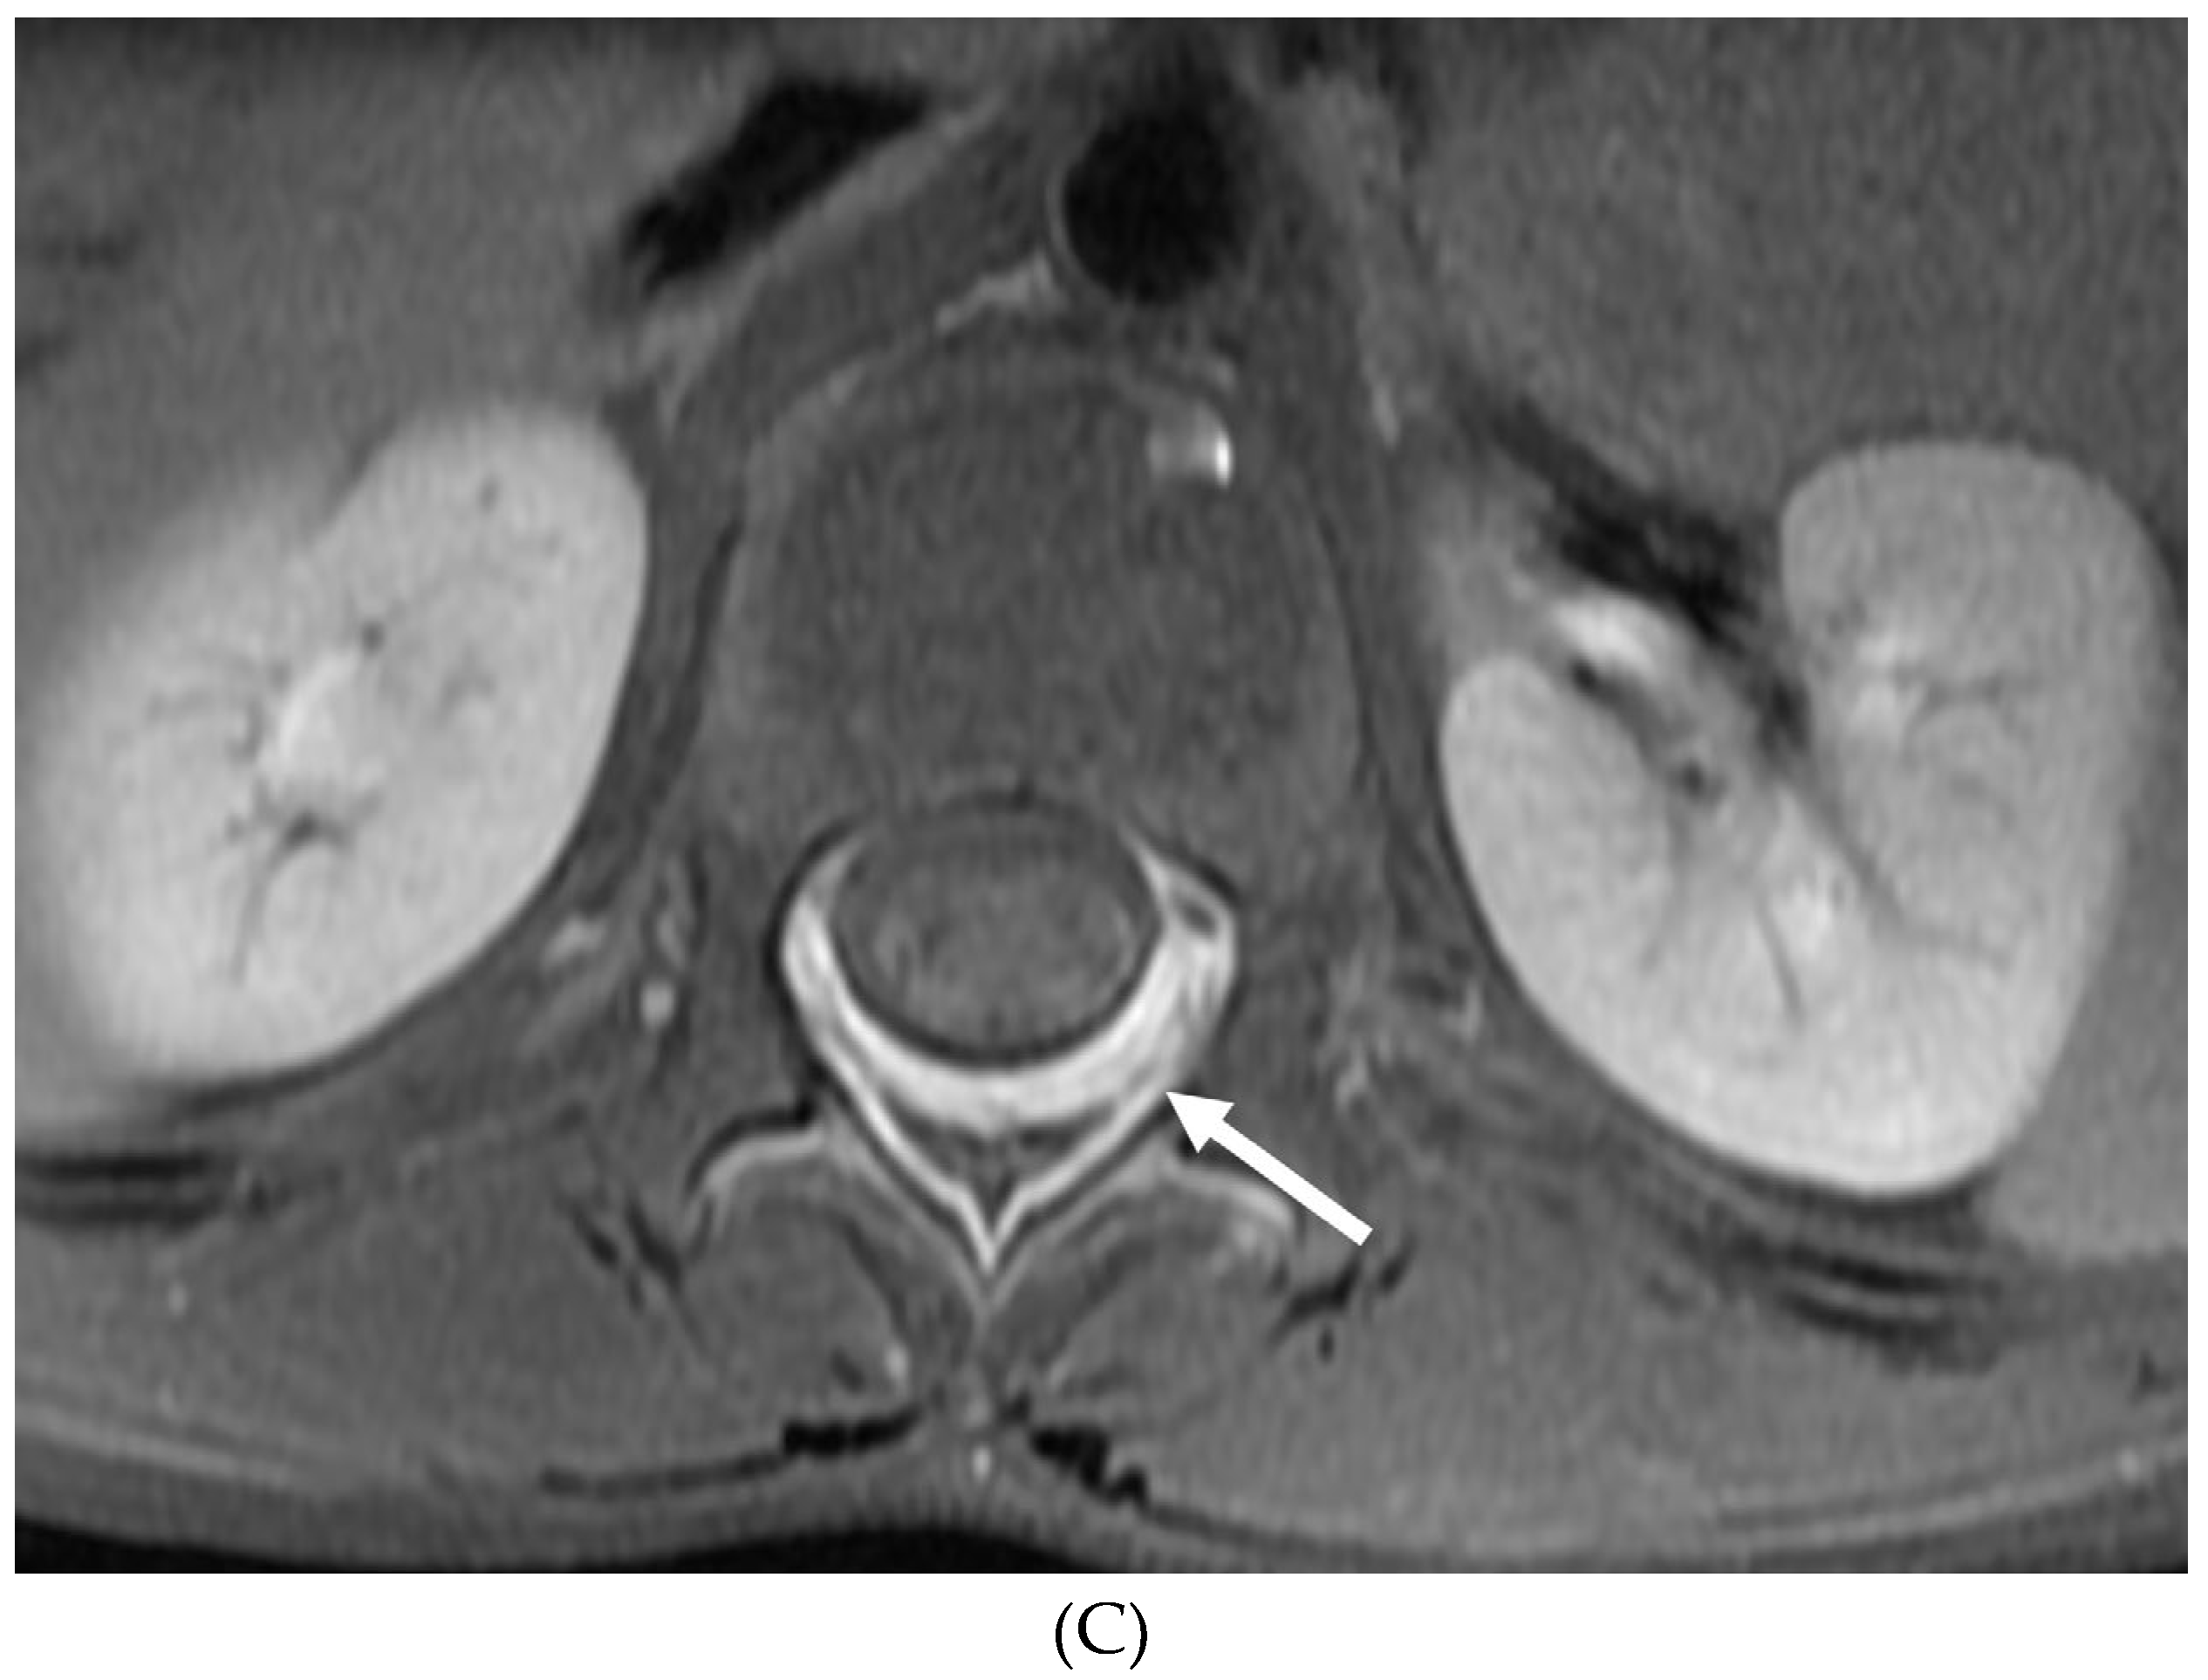

- Alkan O, Yildirim T, Tokmak N, Tan M. Spinal MRI findings of guillain-barré syndrome. J Radiol Case Rep. 2009;3(3):25-8. Epub 2009 Mar 1. PMID: 22470650; PMCID: PMC3303301. [CrossRef]

- Byun WM, Park WK, Park BH, Ahn SH, Hwang MS, Chang JC. Guillain-Barré syndrome: MR imaging findings of the spine in eight patients. Radiology. 1998 Jul;208(1):137-41. PMID: 9646804. [CrossRef]